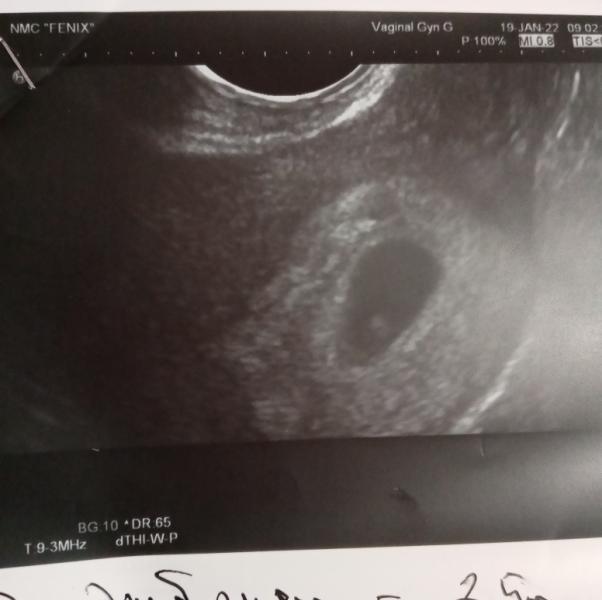

❤️❤️❤️

Первое узи.

13.02.2022